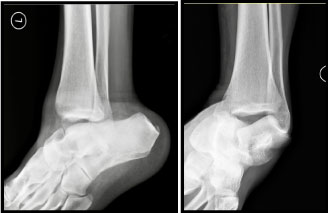

Plain radiographs showed a posterolateral dislocation of talus with a medial malleolus fracture (Figure 2). CT scans showed a tri-articular dislocation with total extrusion of the intact talus from the tibio-talar, talo-calcaneal and talo-navicular joints (Figure 3). There was an associated displaced medial malleolar fracture but no other occult fractures or intra-articular fragments (Figure 4).

Figure 2: Antero-posterior and lateral radiographs of total lateral talar dislocation. View Figure 2